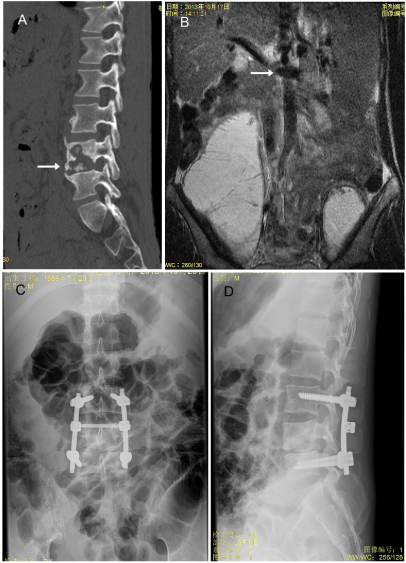

Figure 3. (A). A representative image shows destructed upper thoracic spine (arrow) in a preoperative CT; (B, C). X-ray indicates that lateral and back position of pedicle screws and the fixed spine (arrow) after operation.